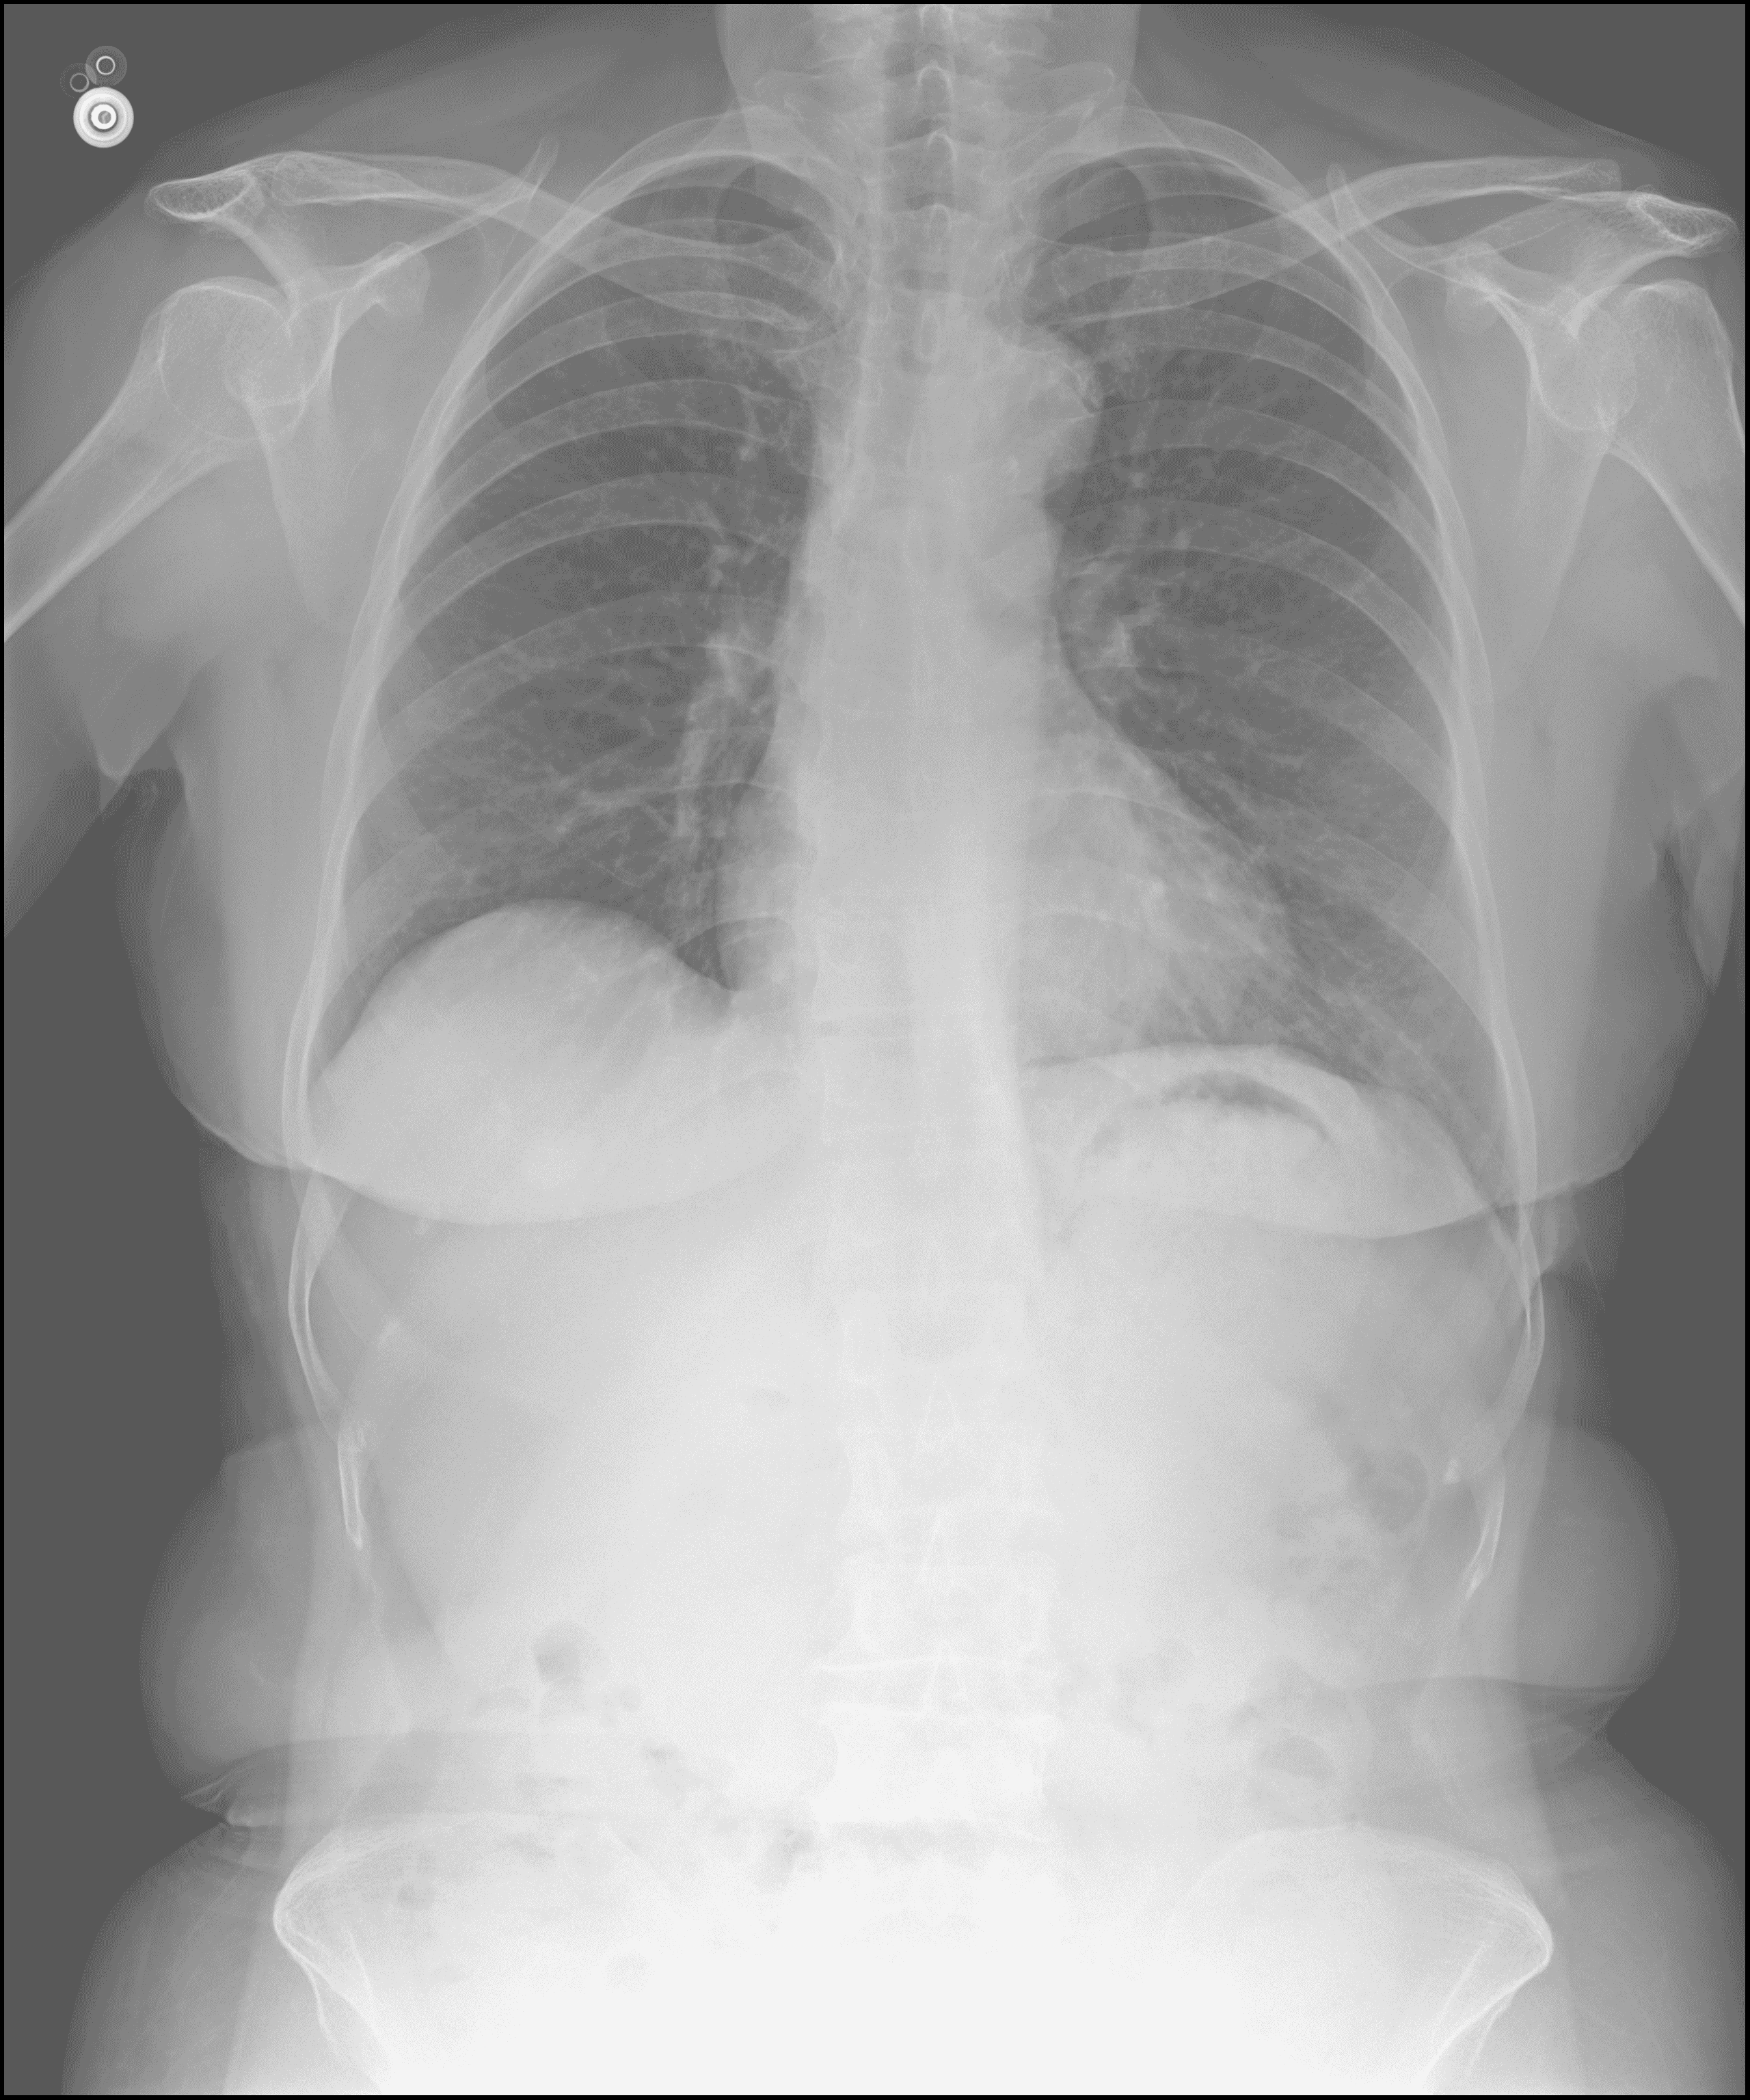

Age 27

Gender Nam - (Male)

View PA (Posterior Anterior)

Note Chụp Xquang ngực thẳng - (Frontal chest X-ray

Technique Chụp Xquang tim phổi thẳng - (Posteroanterior chest radiograph)

Findings Hình ảnh gãy cung xương sườn 2 bên trái. Phổi hai bên kém sáng đều. Thâm nhiễm nhu mô phổi hai bên, đám mờ đông đặc nhu mô phổi phải. Bờ vòm hoành hai bên đều. Góc sườn hoành hai bên nhọn. Bóng tim không to. Các bờ trung thất trong giới hạn bình thường.

(Fracture of the left 2nd rib arch. Both lungs show decreased translucency. Bilateral pulmonary parenchymal infiltrates, with a consolidation opacity in the right lung parenchyma. Both diaphragmatic domes have clear borders. Both costophrenic angles are sharp. The cardiac silhouette is not enlarged. Mediastinal borders are within normal limits.)

Impressions Thâm nhiễm nhu mô phổi hai bên. Đám mờ đông đặc nhu mô phổi phải nghĩ đến đụng dập nhu mô phổi. Gãy cung xương sườn 2 bên trái.

(Bilateral pulmonary parenchymal infiltrates. Consolidation opacity in the right lung parenchyma, suggestive of pulmonary contusion. Fracture of the left 2nd rib arch.)

Table 2: One example from our dataset, ViX-Ray.

3.1.  Data Collection

ViX-Ray was collected from examination records of patients at Vietnam Military Hospital 175, comprising 5,400 chest X-ray images, each accompanied by detailed findings and diagnostic impressions provided by medical specialists. To protect patient confidentiality (Assembly, 2023), all protected health information (PHI) (Isola and Al Khalili, 2023) has been removed to ensure data privacy and security. However, clinically relevant metadata such as age and gender are retained to support diagnostic and analytical tasks. An example from the dataset is presented in Table 2.